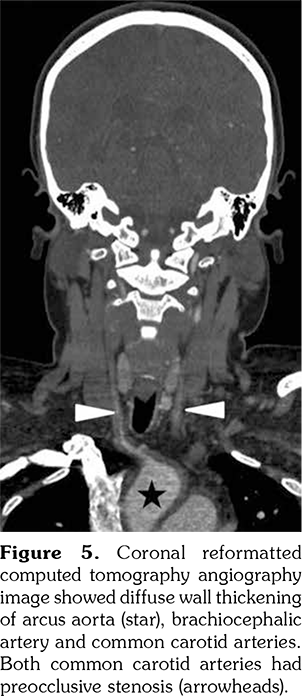

A 14-year-old female patient referred to our clinic with headache and dizziness for two weeks and loss of consciousness for about 10 minutes. On admission, the blood pressure was 90/60 mmHg and all peripheral pulses were palpable. Her body weight was above 97th percentile for her age and body mass index was 33. The fundus examination and other organ systems were essentially normal. Laboratory studies revealed erythrocyte sedimentation rate (ESR) as 108 mm/hour and C-reactive protein (CRP) as 7.5 mg/dL (0-0.8), while other measurements were normal. Urinalysis revealed microscopic hematuria and proteinuria of 31.9 mg/m2/hour in 24-hour urine collection. The cerebrospinal fluid examination showed no abnormalities. Cranial magnetic resonance imaging (MRI) showed multiple millimetric hyperintense deep white matter lesions on T2-weighted imaging (Figure 1). Intracranial and extracranial arteries were normal in magnetic resonance angiography (MRA). Renal biopsy findings were interpreted as FSGS (Figure 2). Patient was considered as cerebral vasculitis and incidental FSGS. Pulse methylprednisolone therapy for three consecutive days was initiated and continued with oral prednisolone. At four years of follow-up, proteinuria decreased to 5-15 mg/m2/hour, and ESR and CRP were normal. Repeated brain MRI and MRA examinations showed no new lesions. Four years later, at the age of 18, on a routine examination, both radial artery pulses were absent and the blood pressure could not be measured. Significant bruit was heard on the left carotid artery. Laboratory studies revealed ESR as 43 mm/hour and CRP as 2.46 mg/dL. Aortic MRA revealed diffuse wall thickening and contrast enhancement in the arcus aorta and its many main branches (Figure 3). Takayasu arteritis diagnosis was established according to the European League Against Rheumatism/ Paediatric Rheumatology International Trials Organisation/Paediatric Rheumatology European Society criteria.[2] Methotrexate was begun, and daily prednisolone was continued. Four months after the diagnosis of TA, left-sided hemiparesis developed. Brain MRI demonstrated a wide cerebral infarct at the right anterior vascular territory (Figure 4). Brain and neck computed tomography angiography showed total occlusion of the right internal carotid artery. Vascular involvement of the right common carotid artery was progressed to preocclusive stenosis. Diameters of the right anterior and middle cerebral arteries were thin and fed by the posterior and anterior communicating arteries (Figure 5). Tocilizumab treatment was started at 8 mg/kg every four weeks. At follow- up with 2.5 years of tocilizumab treatment, the patient's clinical condition improved slightly, and no new symptoms developed. A written informed consent was obtained from the patient.